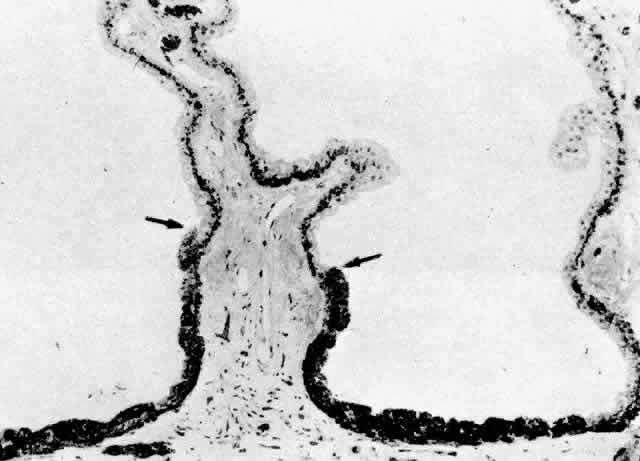

The NPE of the ciliary body stretches in a continuous layer from the root

of the iris to the ora serrata. As the transition from pigmented iris

epithelium occurs, melanin granules in the inner layer suddenly decrease

in number, and the cells become slightly smaller (Fig. 12). In the pars plicata the NPE cells are cuboidal, 12 to 15 μm in width, with

central nuclei (Figs. 13A and 13B). The knobbiness that develops during aging is due to small nodular proliferations

of NPE cells, especially on the minor plicae (Fig. 13C). In the young eye the cells of the pars plana are also cuboidal, but

with growth they become thinner and more columnar, sometimes reaching

up to 30 μm in height and 5 to 10 μm in width (Fig. 13D). In the posterior half of the pars plana, some NPE cells tilt forward

as though responding to anterior zonular traction, while others may be

inclined posteriorly, suggesting complex vectors of force in this region. The

nuclei are vertically oval and lie near the apex of the cells. The

epithelium here becomes very irregular with aging, showing hyperplastic

toothlike cell processes intertwining and extending up into the

vitreous and among the zonular fibers. At the ora serrata the ciliary

NPE joins the retina abruptly, highlighting the difference in thickness

of these two layers (Fig. 14).  Fig. 12. Frontal view of a ciliary process at its junction with iris, showing conversion

to thicker, double-layered iris pigment epithelium (arrows). (Toluidine

blue, X 200) Fig. 12. Frontal view of a ciliary process at its junction with iris, showing conversion

to thicker, double-layered iris pigment epithelium (arrows). (Toluidine

blue, X 200)

Fig. 14. Ora serrata in young adult, showing abrupt junction of ciliary nonpigmented

epithelium and sensory retina. A few hyalocytes are present in the

adjacent vitreous, and a degenerative cyst (C) is present in the peripheral

retina. (Toluidine blue, X 200) Fig. 14. Ora serrata in young adult, showing abrupt junction of ciliary nonpigmented

epithelium and sensory retina. A few hyalocytes are present in the

adjacent vitreous, and a degenerative cyst (C) is present in the peripheral

retina. (Toluidine blue, X 200)